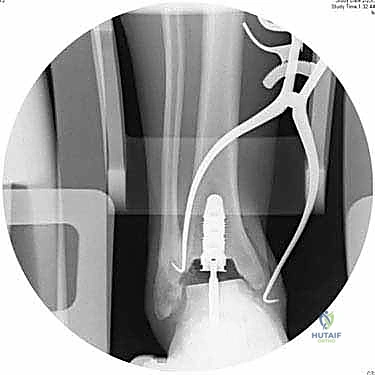

4. إعداد القناة النخاعية وتركيب الساق (Stem)

يتم عمل ثقب دقيق في القناة النخاعية لعظمة الساق. يتم إدخال القطع المعيارية (Modular Stem Pieces) واحدة تلو الأخرى حتى يتم تحقيق التثبيت العميق والمستقر داخل العظم. هذا هو سر قوة نظام INBONE.

6. التحقق والإغلاق

يتم فحص المدى الحركي للكاحل الجديد وثباته تحت جهاز الأشعة السينية (Fluoroscopy) داخل غرفة العمليات للتأكد من المحاذاة المثالية بنسبة 100%. بعد ذلك، يتم إغلاق الشق الجراحي بغرز تجميلية، ووضع جبيرة ناعمة أو حذاء طبي واقٍ.